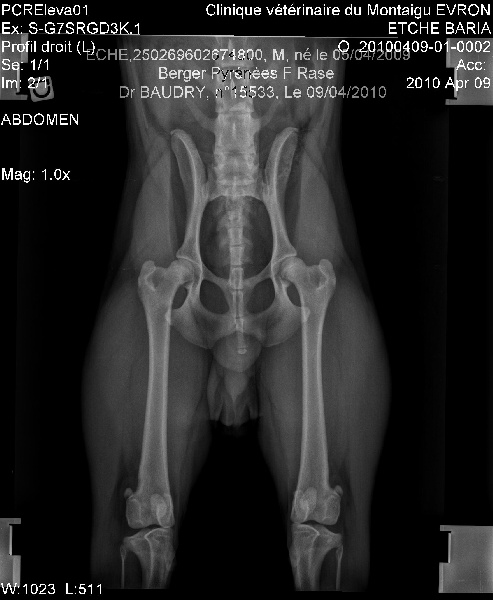

DYSPLASIE COXO-FEMORALE : A/A (exempt de dysplasie) |